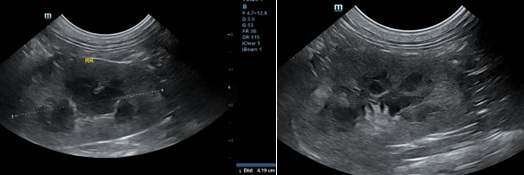

고양이의 신장은 매우 공 같으며, 개보다 유동성이 심합니다. 따라서 프로브를 통해 압박을 가할 때 신장이 빠져나가지 않게 조심스럽게 접근해야 합니다. 중간 주파수의 convex 프로브(7.5-9MHz)로 적절한 영상을 획득할 수 있으며, 더욱 자세한 영상을 얻기 위해서는 보다 높은 주파수의 linear 프로브(10-14MHz)를 이용할 수 있습니다. 그리고 신장은 서로 직각 방향의 방향에서 관찰하는 것이 중요합니다(그림 1 & 2).

정상 신장의 모양은 난원형 혹은 콩 모양을 보이며, 피질(cortex), 수질(medulla) 및 신동(sinus)으로 구분됩니다. 신장의 trans view에선 신우도 관찰할 수 있습니다. 피질은 균일한 에코를 가지며, 간과 비교 시 약간의 저에코 혹은 같은 동에코, 비장과 비교 시에는 저에코성을 보입니다. 정상 고양이에서 근위세뇨관 상피의 지방축적이 많으면 피질의 에코가 증가하여 간보다 에코성이 높아 보일 수 있고, 특히 노령묘, 거세한 수컷과 임신한 고양이에서 이런 현상을 보입니다. 수질은 저에코성~무에코성을 나타내며, 신동은 신문의 중심부로서 지방의 존재로 고에코성을 보입니다.

신우는 보통 보이지 않으나, trans view를 잘 잡으면 보일 수 있습니다(그림 2). 신우의 폭은 1-2mm로 무에코의 선으로 관찰됩니다. 수액 투여 시에는 일시적 확장이 있으며, 결석으로 인한 요도폐색, 종양, 이소성 요관이나 신우신염이 있을 때는 확장이 될 수 있습니다(Table 2, 그림 3). 또한 leptospirosis, 신장의 말기 상태나 신장이식 등에서도 나타날 수 있습니다3).